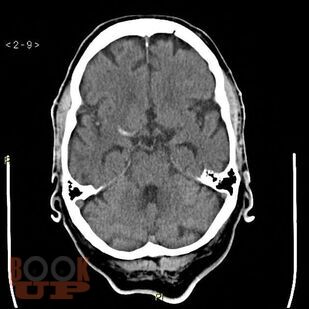

Пособие подготовлено в соответствии с требованиями ФГОС ВО по специальности 31.05.01 Лечебное дело, действующего учебного плана и рабочей программы (2020 г.) для изучения дисциплины «Неврология, нейрохирургия». В нем излагаются современные представления об этиопатогенезе новой коронавирусной инфекции COVID-19, подходы к ее диагностике и лечению, а также клинические особенности поражения нервной системы.

Отдельно рассмотрена организация медицинской помощи пациентам неврологического профиля в условиях распространения COVID-19. Уровень изложения материала соответствует современным требованиям и позволяет оптимизировать организацию и управление самостоятельной работой обучающихся. Пособие содержит тестовые задания и ситуационные задачи, которые помогут в изучении неврологической аспектов COVID-19.